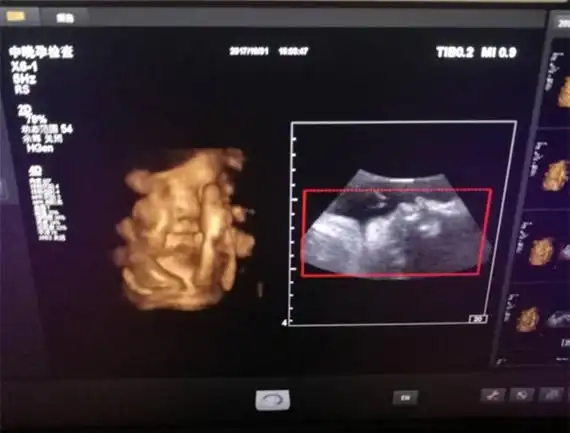

怀孕5个月四维彩超检查, 宝宝完全不配合, 医生直言: 这娃要不得_胎儿

孕26周四维下睾丸的样子 如何看四维彩超识性别

四维彩超,两次发现貌似蛋蛋的两个对称的东西,中间间隔几分钟,再看